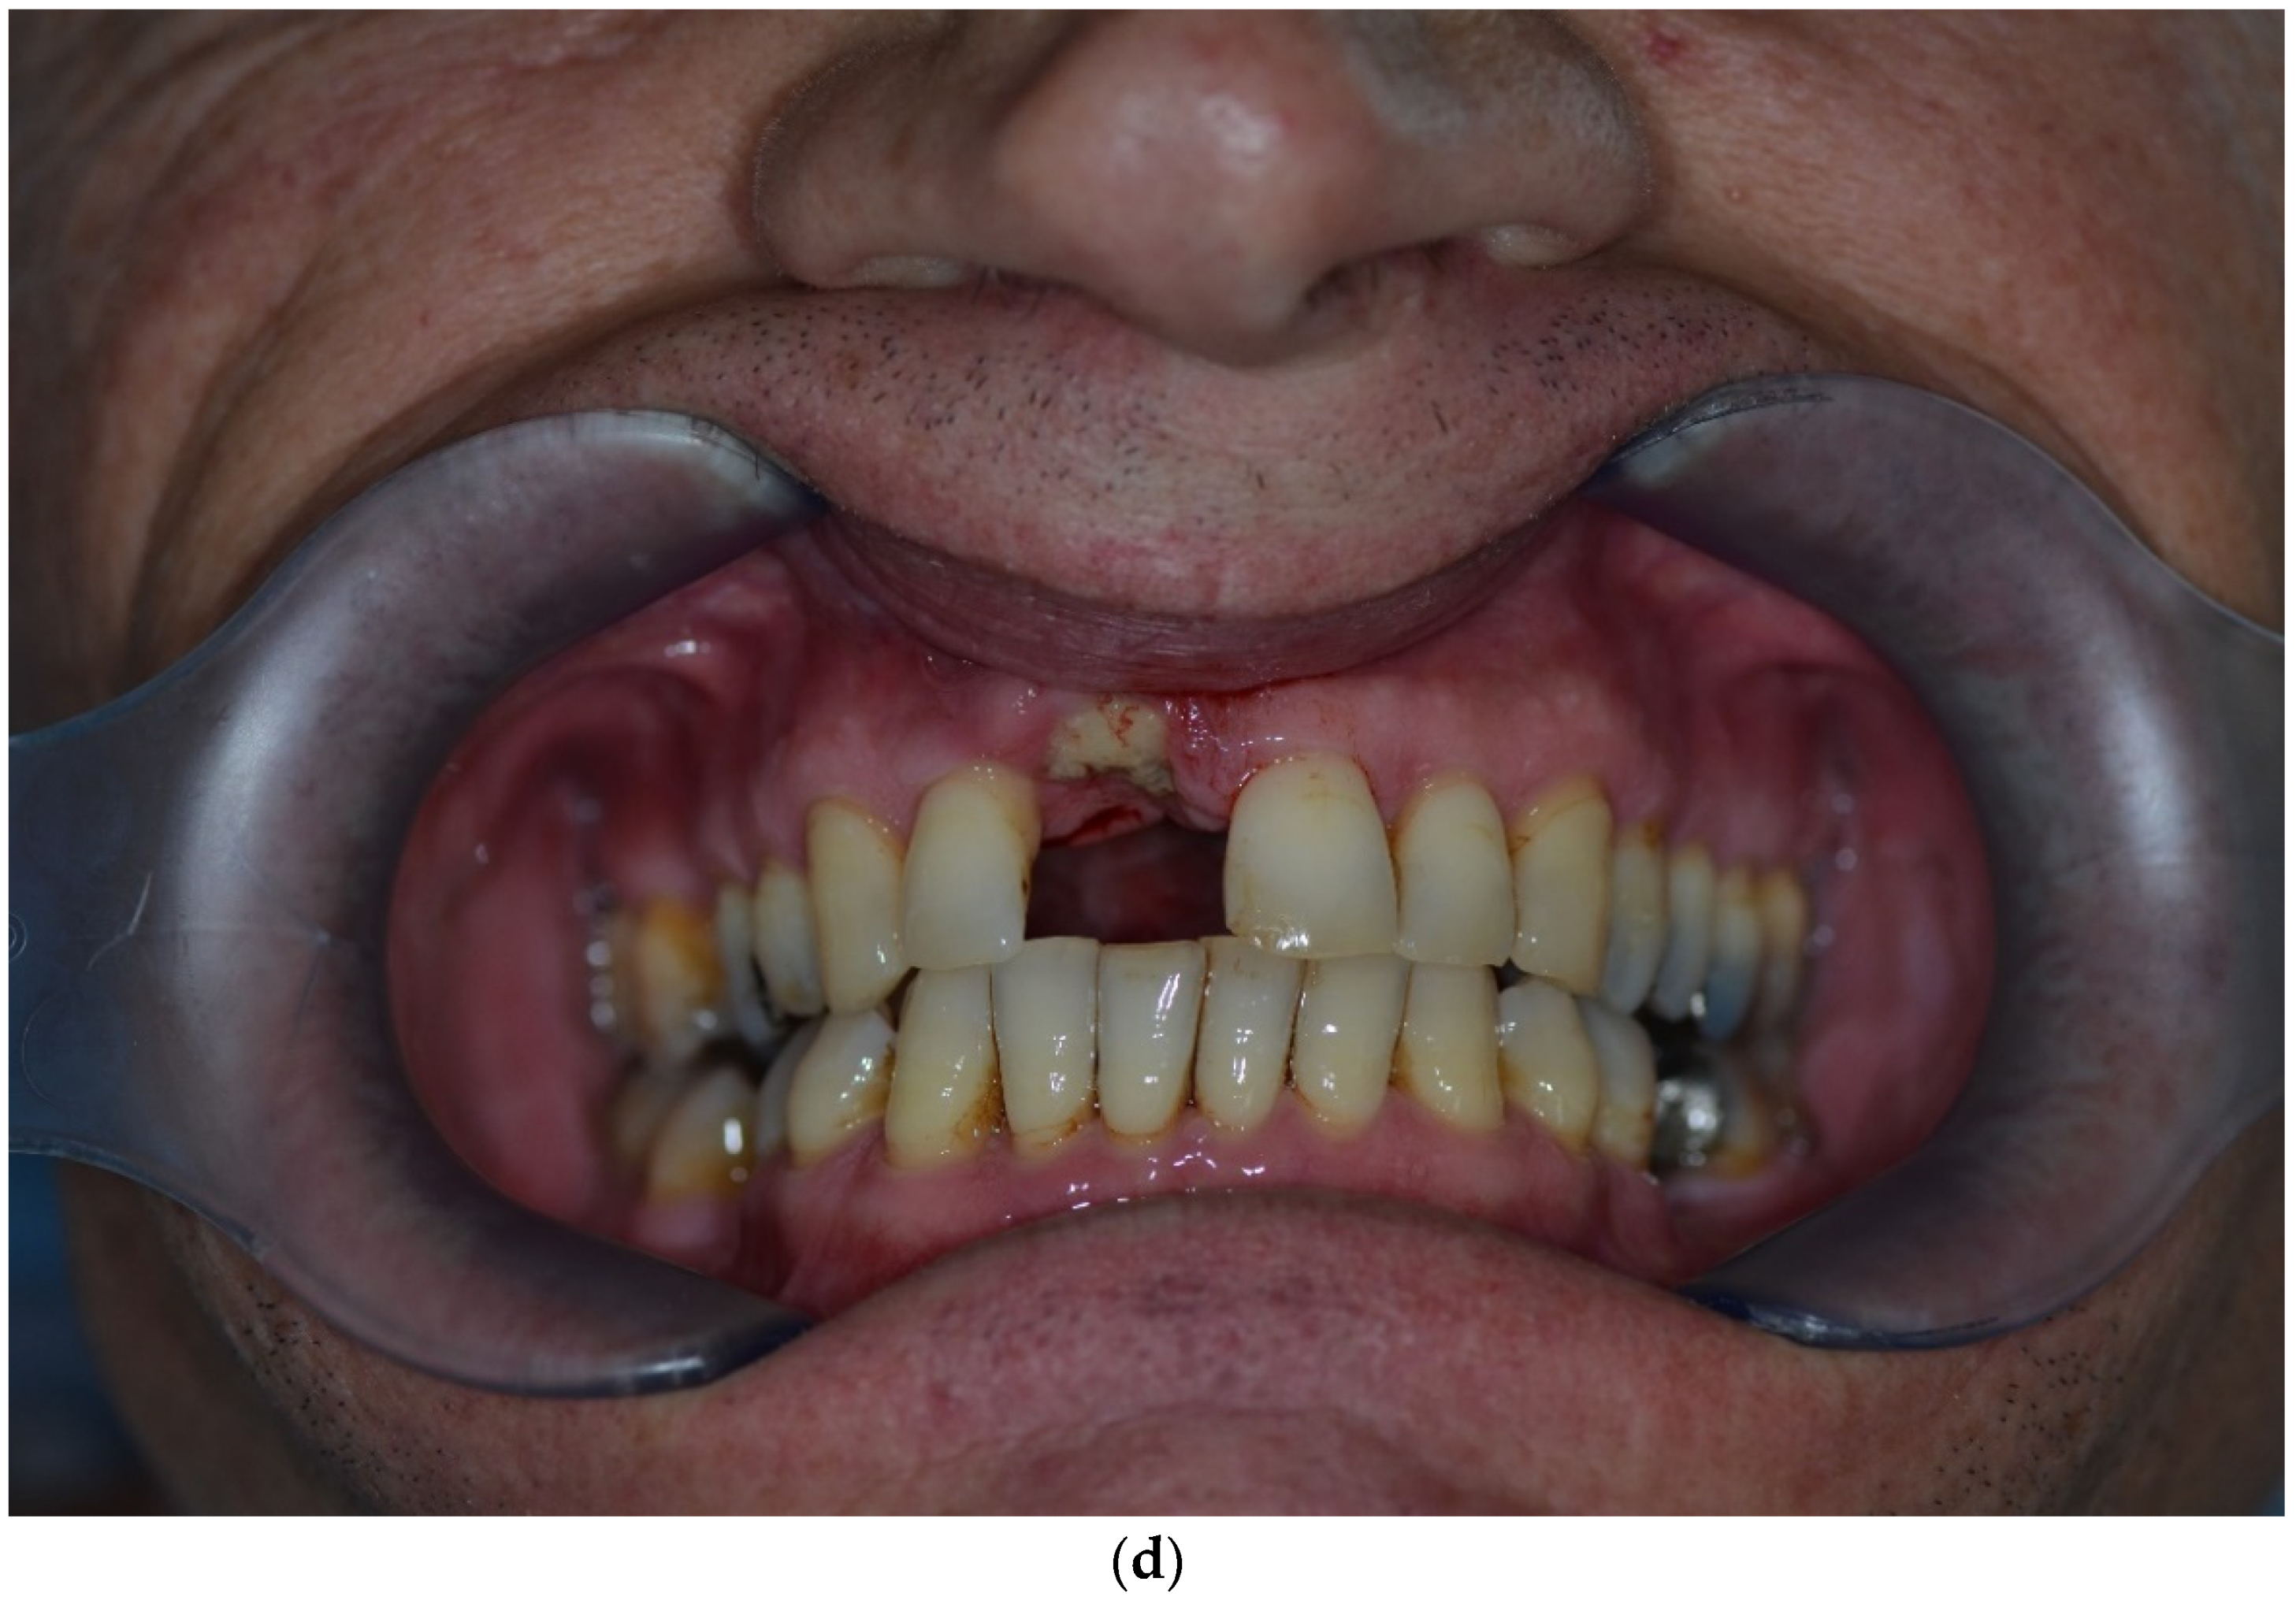

Figure 2.

Clinical example of over-contouring. (a) Class III defect with pronounced vestibular deficit and minor vertical deficit. (b) Post-OP: Attachment of a cortico-cancellous allogeneic bone block. Vestibular over-contouring with the cortical plate and vertical over-contouring of the block can be seen. The block protrudes over the limbus alveolaris, i.e., over the bone border of the adjacent teeth. (c) After 5 months: the over-contoured portion of the cortical portion of the block was not resorbed, but part of the cancellous portion of the block was palatally resorbed away. (d) The over-contoured block penetrates the mucosa. The cortical portion is revealed.